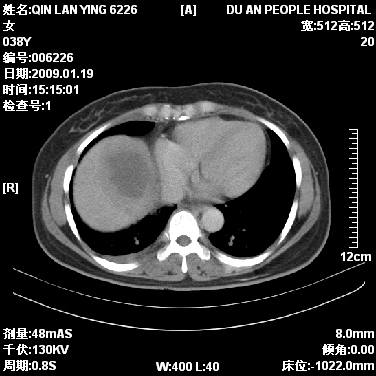

女,38岁,胸疼1个月。wbc:1万4

1)右肺中央型肺癌并右肺上叶阻塞性肺炎、节段性肺不张,纵隔淋巴结转移、右侧胸膜转移、肝脏转移。2)右侧胸腔少量积液。

1、右侧中央型肺癌并阻塞性肺不张,纵隔内、主动脉弓旁、右肺门淋巴结及肝脏转移可能性大,建议纤支镜进一步检查。

2、右侧胸腔积液。

1)右肺中央型肺癌并右肺上叶阻塞性肺炎、节段性肺不张,纵隔淋巴结转移、右侧胸膜转移、肝脏转移。2)右侧胸腔少量积液。支持

从影像学角度分析      右肺上叶中央型肺癌,并阻塞性不张、肺炎,纵隔淋巴结、膈顶淋巴结转移。

肝内两个大小不等低密度结节,内可见更低密度影,首先考虑肝内转移瘤,但联想到患者wbc1万4,建议楼主还是做个增强比较明确,除外肝脓肿的可能。